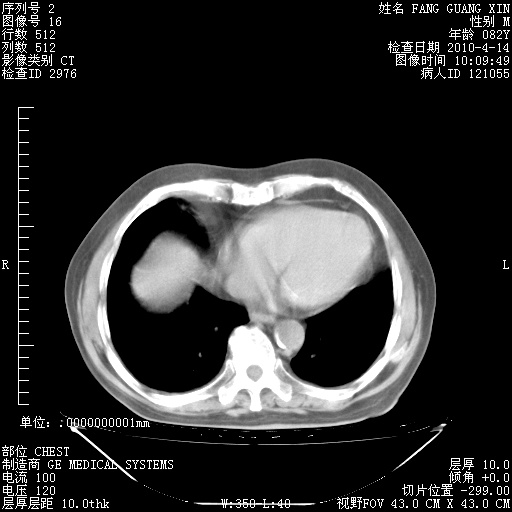

4月28日肺部CT——再次出现类似去年5月9日——透光度降低,(影像科认为)“间质性”改变。

1221483 1 .bmp

1221483 2 .bmp

1221483 3 .bmp

1221483 4 .bmp

1221483 5 .bmp